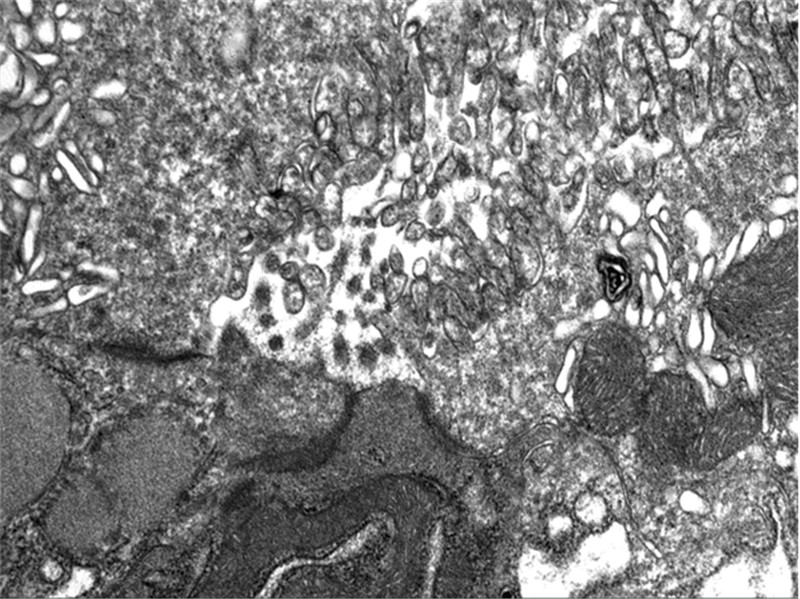

2 结果 2.1 间隙连接电镜超微结构观察结果正常胃组织细胞间连接从腺腔处依次可见紧密连接、桥粒连接和间隙连接;高-中分化胃癌组织细胞间隙连接结构破坏,低分化胃癌组织细胞间隙连接结构严重破坏,见图 1~3。

| 图 1 正常胃组织的间隙连接 (透射电子显微镜×100 000) Figure 1 Complete gap junctions in normal gastric tissues (TEM×100 000) |

| 图 2 高-中分化腺癌中间隙连接破坏不完整 (透射电子显微镜×100 000) Figure 2 Incomplete gap junctions in well-moderately differentiated gastric cancer tissues (TEM×100 000) |

| 图 3 低分化腺癌中间隙连接破坏不完整 (透射电子显微镜×300 000) Figure 3 Incomplete gap junctions in poorly differentiated gastric cancer tissues (TEM×300 000) |

细胞间直接信息传递是通过细胞间连接实现的,细胞间连接包括间隙连接、桥粒连接和紧密连接。紧密连接没有通讯功能,对桥粒连接的通讯功能研究较少,而近年间隙连接的生物学功能备受关注。间隙连接为一种接触面积较大的平板状连接,多见于上皮细胞深部侧表面,此处相邻的细胞膜之间隔以2 nm的间隙,在连接处相邻细胞膜中含有许多大小为6~8 nm呈六角形的颗粒,即连接子(connexon),每一连接子是由6个穿膜的膜内在蛋白质分子围成,中央有直径为2 nm的隧道。相邻细胞质膜上的连接子一一对应相接,隧道相同,构成了细胞间的直接通道,这种微细的管型通道相邻细胞各占一半,并可由6个亚单位以相互滑动的方式开启或关闭[5]。我们通过电子显微镜对正常胃组织和胃癌组织进行超微结构观察发现:正常的胃黏膜间隙连接结构完整而胃癌的间隙连接结构遭到破坏,并且分化差的胃癌组织间隙连接结构遭到破坏较重,因此可以推断因细胞的间隙连接通讯功能缺失,细胞发生转化后其细胞间隙连接通讯功能降低或抑制,可能是促癌变阶段的重要机制,缝隙连接的缺乏可能参与了肿瘤的发生。